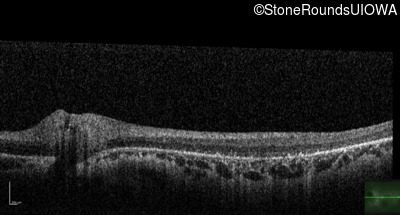

Age at visit: 10 years

OD OS